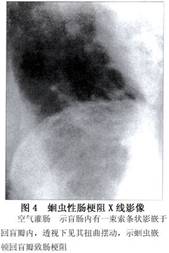

腸內蛔蟲扭結成團造成機械性梗阻,加上蛔蟲的局部刺激引起痙攣,故X線腹平片影像表現爲:①梗阻多發生於小腸低位,且以不完全性梗阻爲多。②立位腹片有時在液平面上方可見波浪狀或粗顆粒狀不平整,密度不均勻影(圖1),呈典型“駝峯”徵,此多爲蟲團所致。③大部分蛔蟲性腸梗阻病人的腹片上可見各種蟲體姿態,或成索條狀排列,或蜷曲成團。見到大小相似粗顆粒狀蟲體斷面影,形態不斷變化。蟲體5~6mm粗,如蟲體吞氣可見蟲體內有線形或點狀氣影(圖2)。如蟲體吞鋇,待病人腸內鋇排盡後,則可見許多線形或點狀鋇影。④蟲團在腸管內也可引起痙攣,蠕動紊亂,導致腸扭轉,甚至發展至絞窄、壞死。⑤嵌頓在迴盲瓣內的蛔蟲,由於迴盲瓣痙攣,蛔蟲難以通過,臨牀表現劇烈痙攣痛,X線下可見成束蛔蟲被嵌於迴盲瓣(圖3,4)。⑥如腸壞死穿孔,可在周圍氣腹或膿腫氣腔內見到蜷曲蛔蟲影(圖5)。